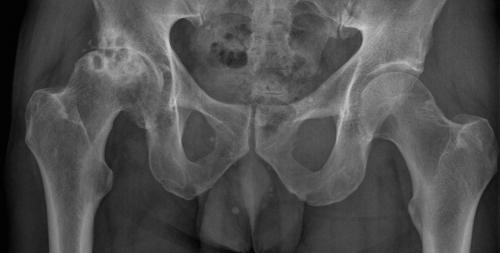

Коксартроз правого тазобедренного сустава 3-й степени (на снимке — слева).